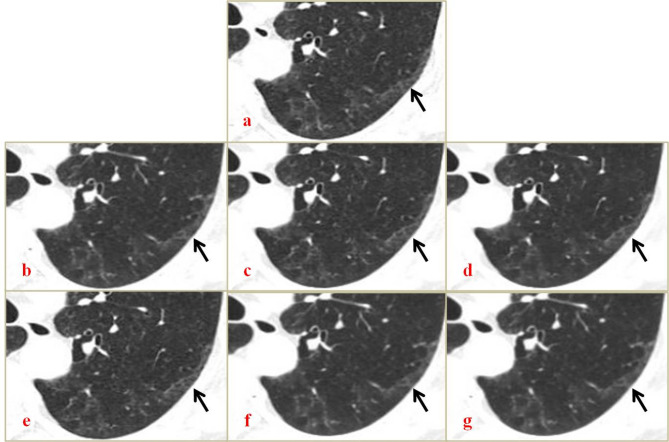

Methods: This study prospectively enrolled 21 patients with early-stage ILD. All patients underwent high-resolution CT (HRCT) and low-dose CT (LDCT) scans. HRCT images were reconstructed with HIR using standard settings, and LDCT images were reconstructed with DLR (lung/bone kernel) in a mild, standard, or strong setting. Overall image quality, image noise, streak artifacts, and visualization of normal and abnormal ILD features were analysed.

Results: The effective dose of LDCT was 1.22 ± 0.09 mSv, 63.7% less than the HRCT dose. The objective noise of the LDCT DLR images was 35.9-112.6% that of the HRCT HIR images. The LDCT DLR was comparable to the HRCT HIR in terms of overall image quality. LDCT DLR (bone, strong) visualization of bronchiectasis and/or bronchiolectasis was significantly weaker than that of HRCT HIR (p = 0.046). The LDCT DLR (all settings) did not significantly differ from the HRCT HIR in the evaluation of other abnormal features, including ground glass opacities (GGOs), architectural distortion, reticulation and honeycombing.